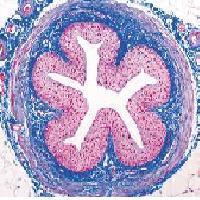

La esterilización es un proceso esencial para el funcionamiento de un hospital, en el cual se deben utilizar todos los instrumentos quirúrgicos, implantes y muchos otros dispositivos absolutamente esterilizados. La desecación y la congelación eliminan muchas especies de bacterias, pero otras simplemente permanecen en estado vegetativo. El calor seco o húmedo elimina todas las bacterias combinando adecuadamente factores como la temperatura a la que se someten y el tiempo de exposición. Se puede esterilizar por calor seco en estufas a más de 160 °C durante media hora, o por calor húmedo en autoclaves a 120 °C durante 20 minutos y a presión superior a la atmosférica. La ebullición a 100 °C no elimina todos los gérmenes patógenos (entre los que no sólo están incluidas las bacterias sino también virus y levaduras). Otro medio habitual de esterilización, utilizado para objetos no resistentes al calor, son los medios químicos: el ácido fénico, iniciador de la era de la antisepsia (véase Fenol), el ácido cianhídrico (véase Cianuro de hidrógeno), el óxido de etileno, la clorhexidina, los derivados mercuriales, los derivados del yodo (especialmente la povidona yodada) y muchas otras sustancias. El alcohol etílico no produce esterilización completa. Otro medio de esterilización actual son las radiaciones ionizantes (beta, gamma).